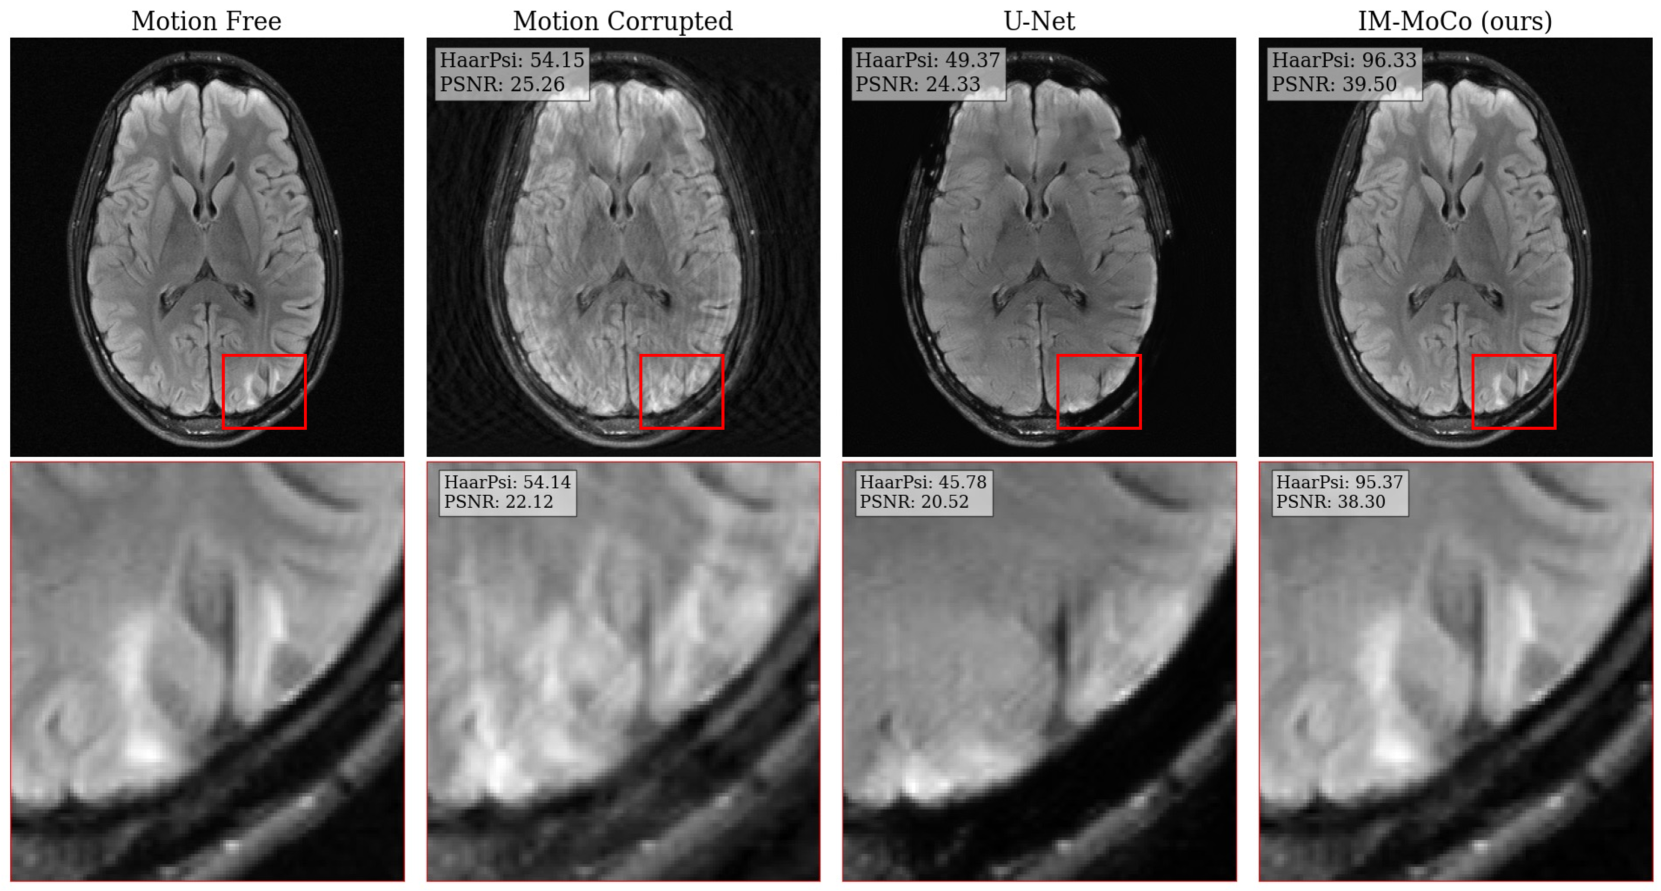

Experiment II: Downstream Classification Task. In this experiment, we demonstrate clinical relevance with a classification of pathologies in motion and motion-corrected images. We extract patches of size 124×124124124124\times 124124 × 124 around bounding boxes of the fastMRI+ dataset and normalized between [0,1]01[0,1][ 0 , 1 ]. We used a pre-trained ResNet18 (PyTorch Hub222https://pytorch.org/hub/pytorch˙vision˙resnet/) backbone for feature extraction and added two trainable linear layers as the classification head. Using the SGD optimizer, we trained the model for 100100100100 epochs with a batch size of 20202020 and a learning rate of 1e31superscript𝑒31e^{-3}1 italic_e start_POSTSUPERSCRIPT - 3 end_POSTSUPERSCRIPT. The trained model is then applied to the test set. We report the SSIM, PSNR, and HaarPSI for extracted patches around the bounding boxes and accuracy for the classification.

Experiment II: Downstream Classification Task.

The results are summarized in Table 2. Motion-free images achieve an accuracy of 97%percent9797\%97 %. For corrupted images, the accuracy is 96%percent9696\%96 % for light and 94%percent9494\%94 % for heavy motion, which is due to image quality loss as reflected in SSIMs of 89%percent8989\%89 % and 77%percent7777\%77 %, respectively. The U-Net’s accuracy is 90%percent9090\%90 % for light and 88%percent8888\%88 % for heavy while its SSIMs are 87%percent8787\%87 % and 79%percent7979\%79 %. IM-MoCo achieves an accuracy of 97%percent9797\%97 % for light and 96%percent9696\%96 % for heavy motion, with the highest SSIMs of 99%percent9999\%99 % and 95%percent9595\%95 %, respectively.

Table 2: Quantitative results of experiment II: image quality and classification accuracy improvements in patches of the fastmri+ annotations. The arrows indicate the direction of improvement.

Scenario Method SSIM\uparrow PSNR (db)\uparrow HaarPSI\uparrow Accuracy\uparrow

Motion-free n.A. n.A. n.A. n.A. 97.1697.1697.1697.16

Light Motion corrupted 89.93±4.67plus-or-minus89.934.6789.93\pm 4.6789.93 ± 4.67 28.29±4.07plus-or-minus28.294.0728.29\pm 4.0728.29 ± 4.07 76.12±9.95plus-or-minus76.129.9576.12\pm 9.9576.12 ± 9.95 96.3296.3296.3296.32

U-Net [1] 87.37±4.31plus-or-minus87.374.3187.37\pm 4.3187.37 ± 4.31 25.80±2.61plus-or-minus25.802.6125.80\pm 2.6125.80 ± 2.61 70.87±7.74plus-or-minus70.877.7470.87\pm 7.7470.87 ± 7.74 90.4490.4490.4490.44

IM-MoCo (ours) 99.00±1.82plus-or-minus99.001.82\mathbf{99.00\pm 1.82}bold_99.00 ± bold_1.82 44.82±6.44plus-or-minus44.826.44\mathbf{44.82\pm 6.44}bold_44.82 ± bold_6.44 97.33±5.56plus-or-minus97.335.56\mathbf{97.33\pm 5.56}bold_97.33 ± bold_5.56 97.0697.06\mathbf{97.06}bold_97.06

Heavy Motion corrupted 77.03±5.74plus-or-minus77.035.7477.03\pm 5.7477.03 ± 5.74 23.56±2.18plus-or-minus23.562.1823.56\pm 2.1823.56 ± 2.18 58.87±6.20plus-or-minus58.876.2058.87\pm 6.2058.87 ± 6.20 94.1294.1294.1294.12

U-Net [1] 79.45±4.50plus-or-minus79.454.5079.45\pm 4.5079.45 ± 4.50 23.70±2.18plus-or-minus23.702.1823.70\pm 2.1823.70 ± 2.18 59.82±5.88plus-or-minus59.825.8859.82\pm 5.8859.82 ± 5.88 88.2488.2488.2488.24

IM-MoCo (ours) 95.26±3.31plus-or-minus95.263.31\mathbf{95.26\pm 3.31}bold_95.26 ± bold_3.31 34.56±5.61plus-or-minus34.565.61\mathbf{34.56\pm 5.61}bold_34.56 ± bold_5.61 88.48±7.80plus-or-minus88.487.80\mathbf{88.48\pm 7.80}bold_88.48 ± bold_7.80 96.3296.32\mathbf{96.32}bold_96.32